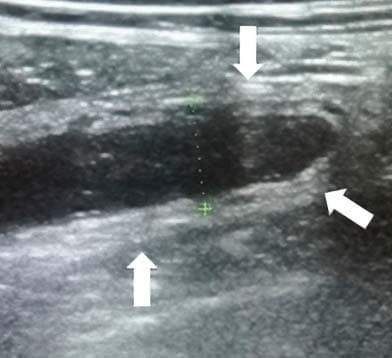

Воспаленный аппендикс не поддается компрессии, поэтому его размер и форма остаются прежними (трубчатая структура на продольном скане и круглая на поперечном) (см. рис. 4).

Рисунок 4. Оценка сжимаемости.